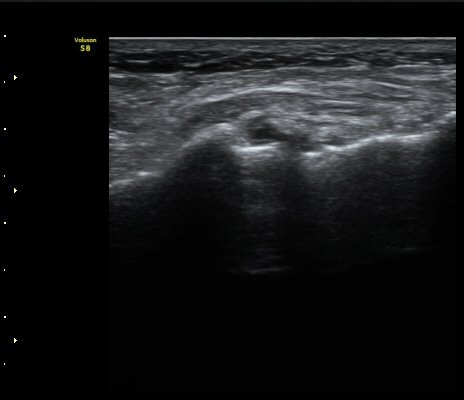

ÃÊÀ½ÆÄ °Ë»ç

Á¾°ñÀÔ¹æ°ñÀδëÀÇ Á¾´Ü¸é°Ë»ç¿¡¼­ ÀδëÀÇ Á¾°ñ ºÎÂøºÎ ÆÄ¿­ÀÌ °üÂûµÊ(»çÁø 1, 2, 3).